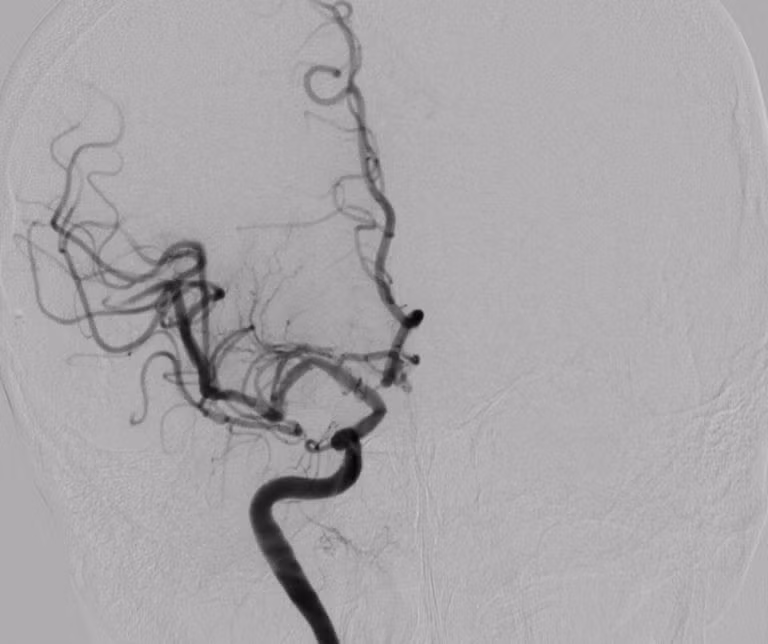

dot-quy-cao-3.jpg

Hình DSA cho thấy hẹp nặng đoạn gốc động mạch cảnh trong ngoài sọ trước can thiệp của bệnh nhân đột quỵ.